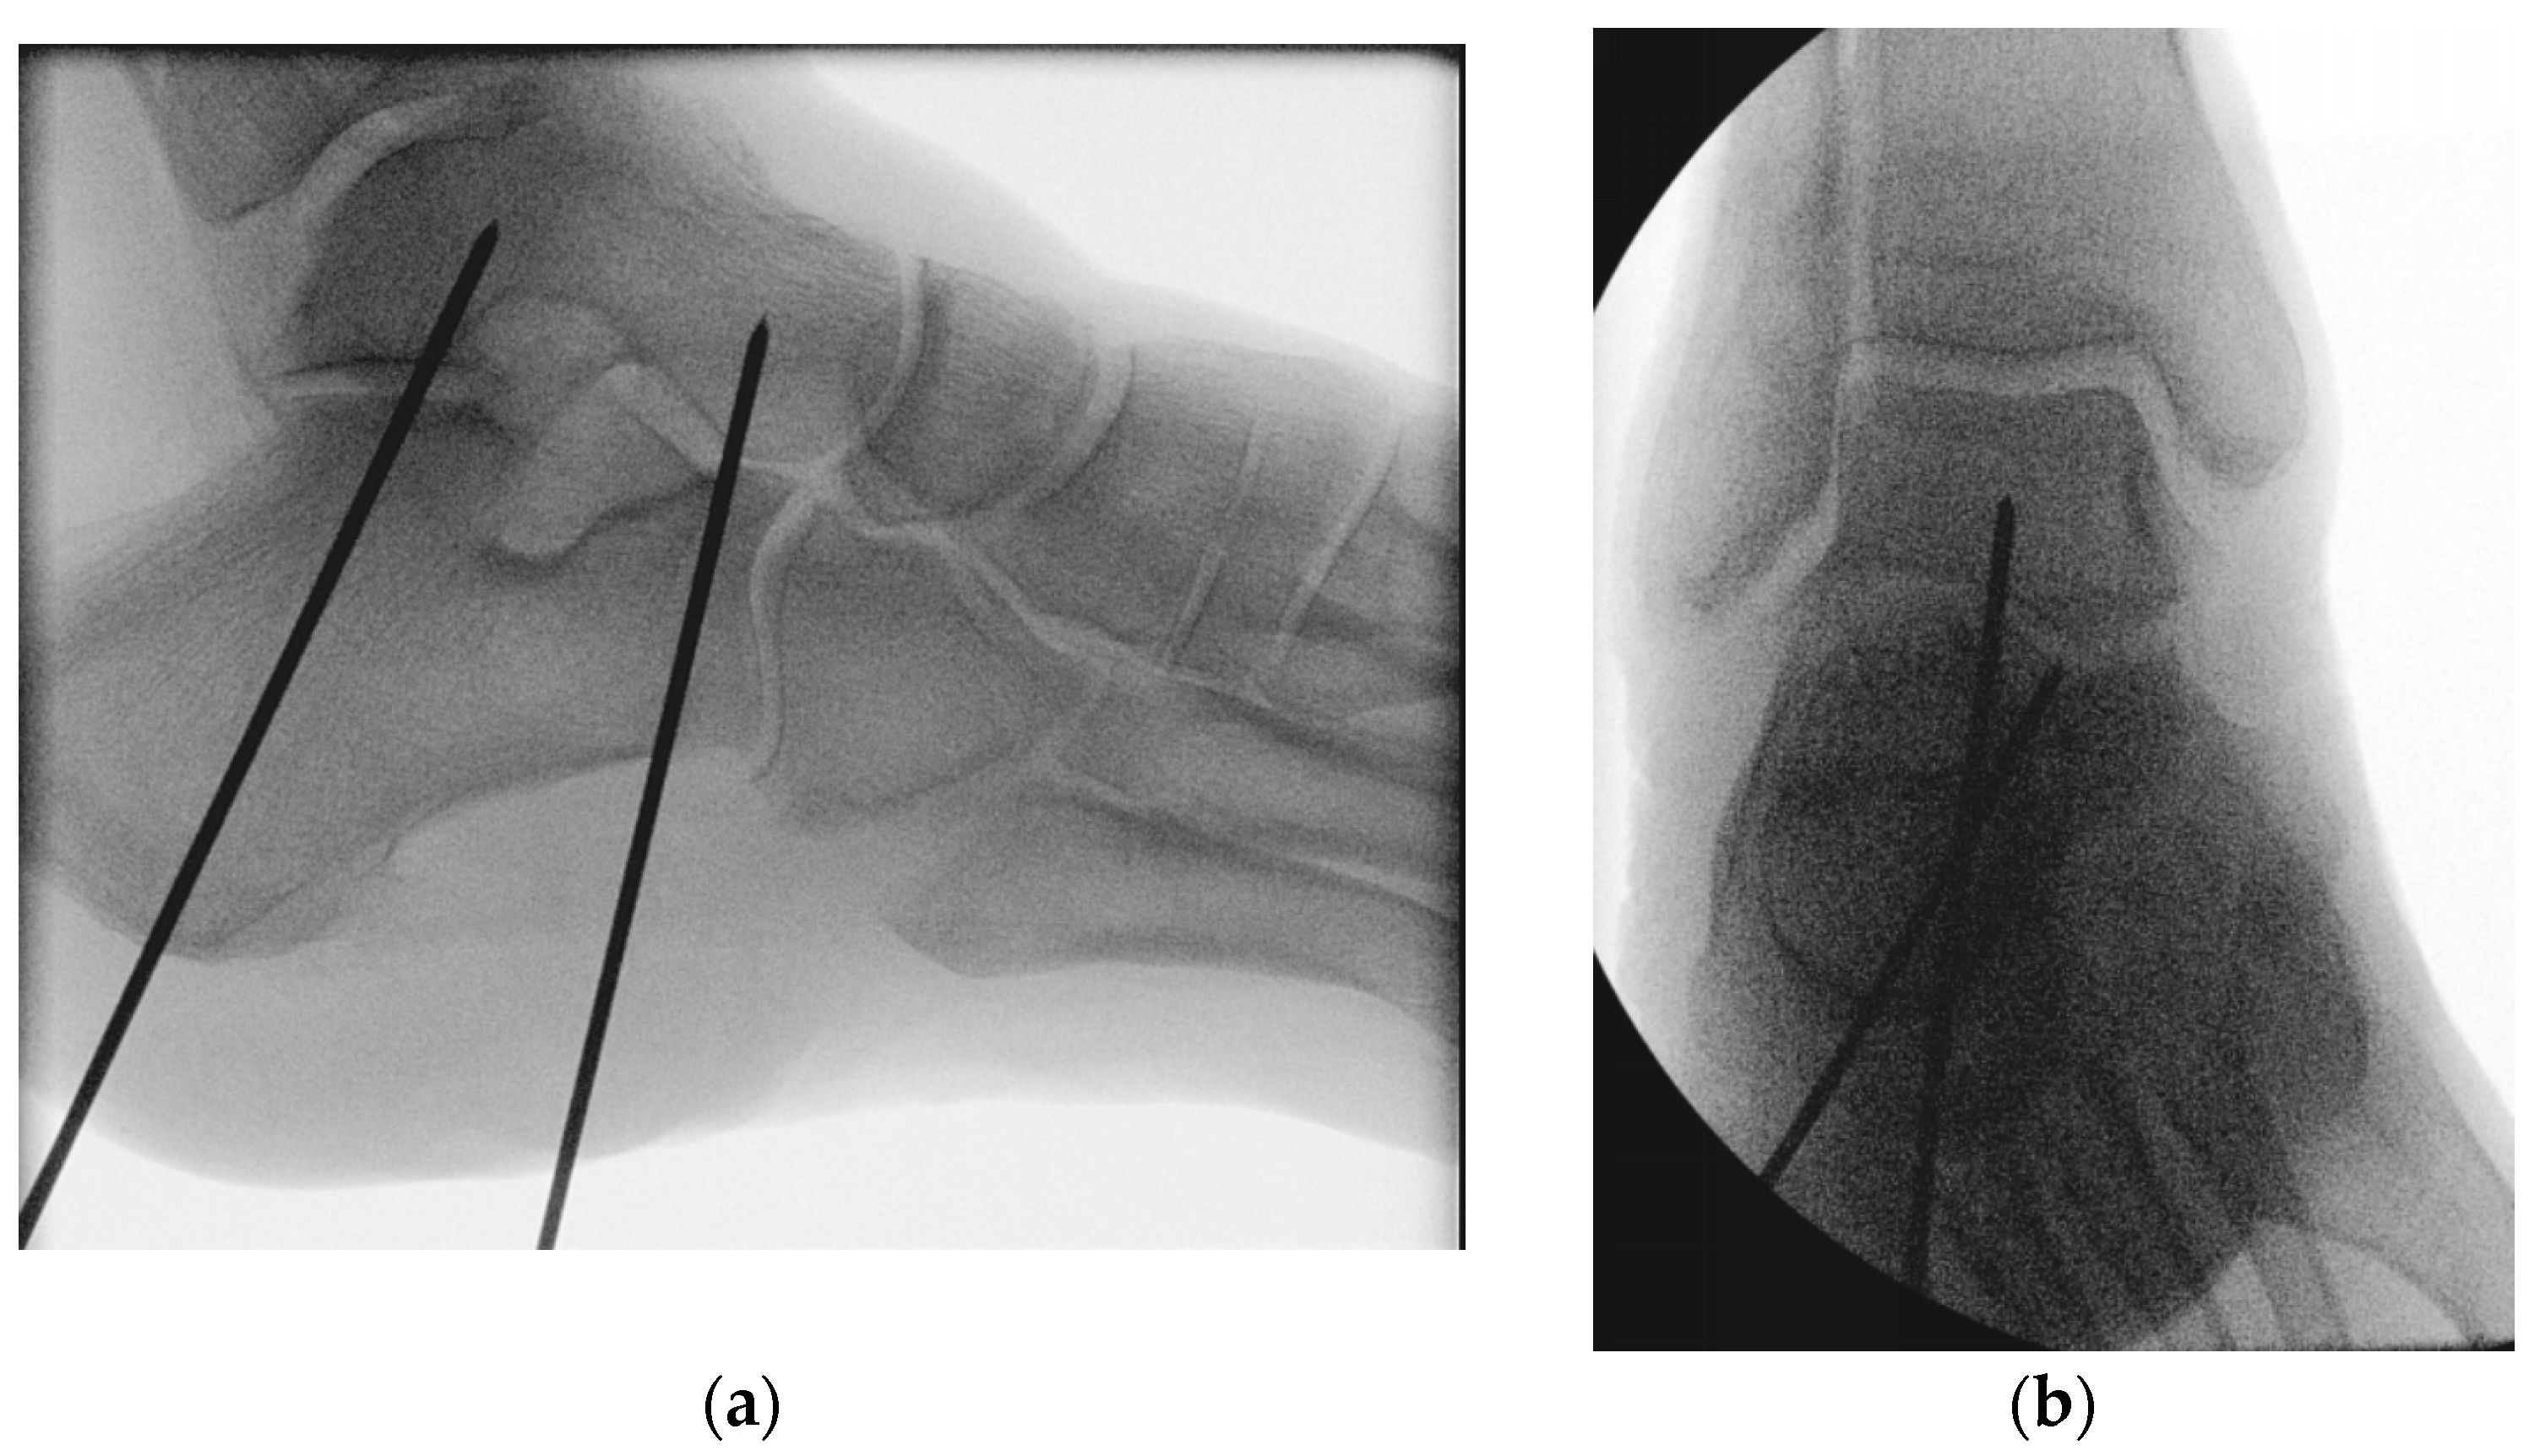

Two 2 mm guide wires were placed and consequently joint fixation was conducted in a highly divergent delta configuration [29]. The insertion point of the first guide wire was located at the center of the calcaneal tuberosity. The wire was directed across the posterior facet of the subtalar joint at a 90° angle, with its tip located in the center of the talar dome [30]. The insertion point of the second guide wire was located at the lateral plantar aspect of the anterior calcaneus, 10 mm proximal to the calcaneocuboid joint. The wire was directed at an approximate angle of 45°, passing dorsally and medially (parallel to the Chopart’s joint line) to the head and neck of the talus [15]. Predrilling was then performed along the guide wires with a 4 mm gauge [31] (Figure 4).

Figure 4.

Radiographs visualizing the positioning of the two 2 mm guide wires used for screw insertion with delta configuration during subtalar joint arthrodesis in lateral (a) and anteroposterior (b) views.